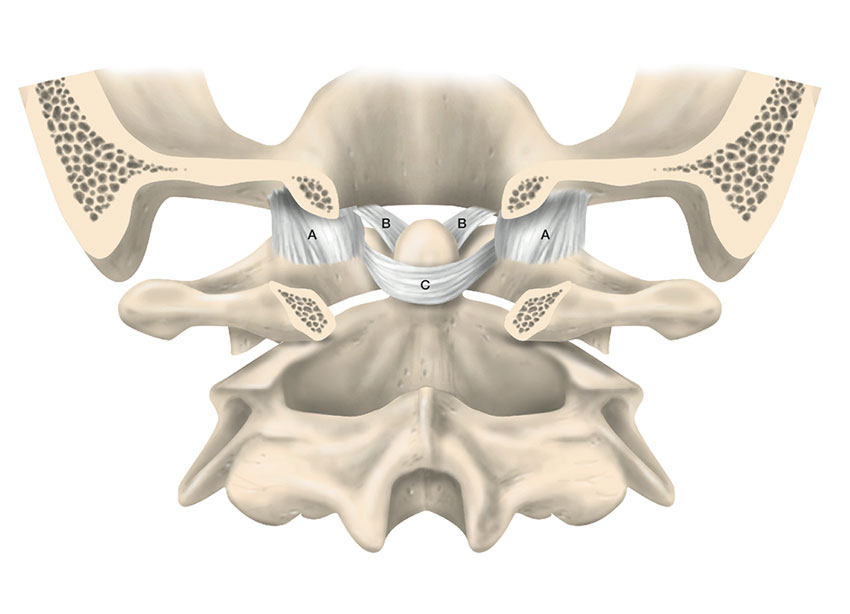

Halsryggens stabiliserande ligamentkomplex tillåter ett stort rörelseuttag samtidigt som det begränsar rörelse utanför ändlägena. Atlanto-occipitalt finns ett system av ligament och ledkapslar som förhind­rar överrörlighet mellan skalle och halsrygg. Ligamentum transversum (i det kruciforma ligamentet) är kraftigast och fixerar dens axis till atlas tillsammans med ligamentum alare och förhindrar instabilitet mellan C1 och C2. Nedanför C2 utgörs stabiliteten framför allt av de diskoligamentära komplexen, omfattande intervertebraldiskar, anteriora longitudinella ligament (ALL), posteriora longitudinella ligament (PLL), ligamentum flavum, interspinala ligament samt fasettledernas ledkapslar [9].

Ligamentapparaten i övre halsryggen. A) C0–C1-kapseln. B) Ligamentum alare. C) Ligamentum transversum.